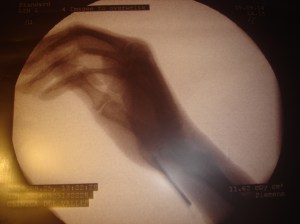

imagen intraoperatoria en la que se puede ver la aguja de implantación

era muy satisfactorio para la paciente (aunque en la mano derecha era muy bueno pero persistía algo de dolor). Luego de 4 meses, en el momento de colocar implantes en las rodillas se colocó un implante más en la cara palmar de la articulación metacarpofalángica que era algo sintomática. Se puede ver en la RX interaoperatoria. El resultado inmediato ha sido muy satisfactorio.